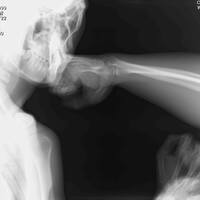

パンチドランカー(3)パンチドランカーチェックリスト11

パンチドランカー、予防に勝る治療なし。 【パンチドランカーチェックリスト11】 格闘技医学会では、11項目のパンチドランカーチェックリストを作成し、現場での意識向上にご活用いただいています。これらが大丈夫であれば、パンチドランカーにならないというものではありません。これらの項目に気を配りながら、身体…